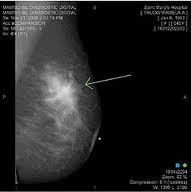

Most recently, a 36-year old woman I work with was diagnosed with stage IV, lobular breast cancer. She knew something was wrong and could not get doctors and other health care providers to pay attention; saying to her when she pointed out the lump on her neck and the one just above her breast, we’ll wait and see. Shame on those doctors for not immediately taking action!!

Now, I must use more than one hand to count the number of women I know who have breast cancer. Co-workers, friends of friends, and at least one of my very good friends from college (Llama). Ladies, I encourage you to be sure you do your self-exams every month and have your mammogram done!